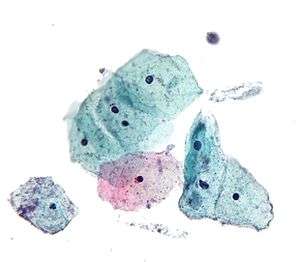

Normal squamous epithelial cells in premenopausal women

Atrophic squamous cells in postmenopausal women